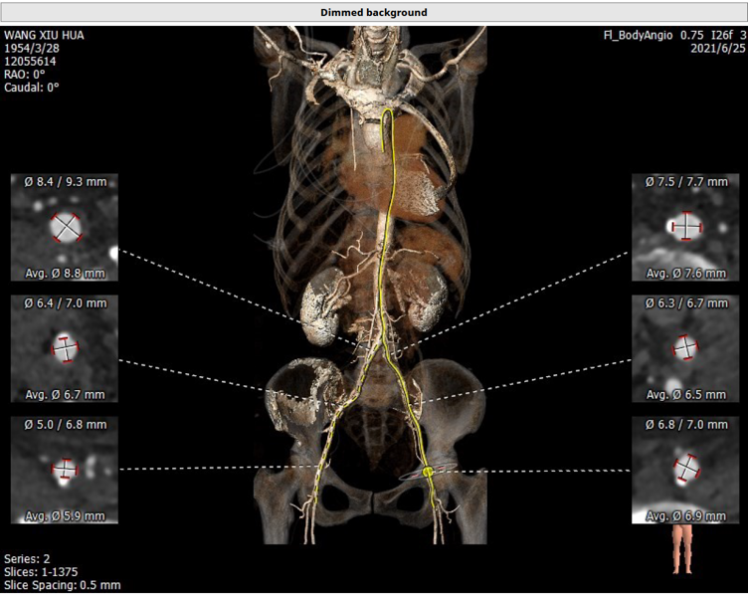

3. 全主动脉入路CT评估(图3)

(二)二尖瓣位评估:

测量perimount 27瓣膜瓣环,同时评估拟植入26型号SAPIEN 3瓣膜对于左室流出道的影响,还有生物瓣投射角度分析,房间隔穿刺及距离二尖瓣生物瓣的距离分析,详细见下图(图6)。